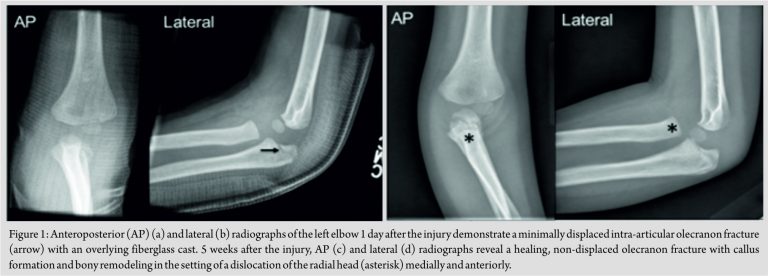

A 3-year-old male was seen in the emergency department with left elbow pain following a fall from a sofa. No prior injuries or significant medical history were noted. On physical examination, the skin was intact with soft and compressible compartments. The patient was neurovascularly intact with normal sensation and strength of the median, radial, and ulnar nerves and associated musculature. Plain radiographs at the time were read as a “minimally displaced olecranon fracture” (Fig. 1a and b). While the lateral view shows an intact radiocapitellar line, the AP view shows that the radius is medial to the capitellum. This radial head dislocation was not recognized at the time. The patient was placed in a bivalve long arm cast and scheduled to follow-up in clinic in 1 week; however, he missed the original follow-up appointment. 5 weeks after the initial injury, the patient followed up in clinic. By that time, the physical examination showed limited range of motion with arm flexion to 90°, extension to 40°, and a 20° pronation/supination arc. Repeat radiographs demonstrated an intra-articular olecranon fracture with a radial head dislocation and disruption of the proximal radioulnar joint (Fig. 1c and d).